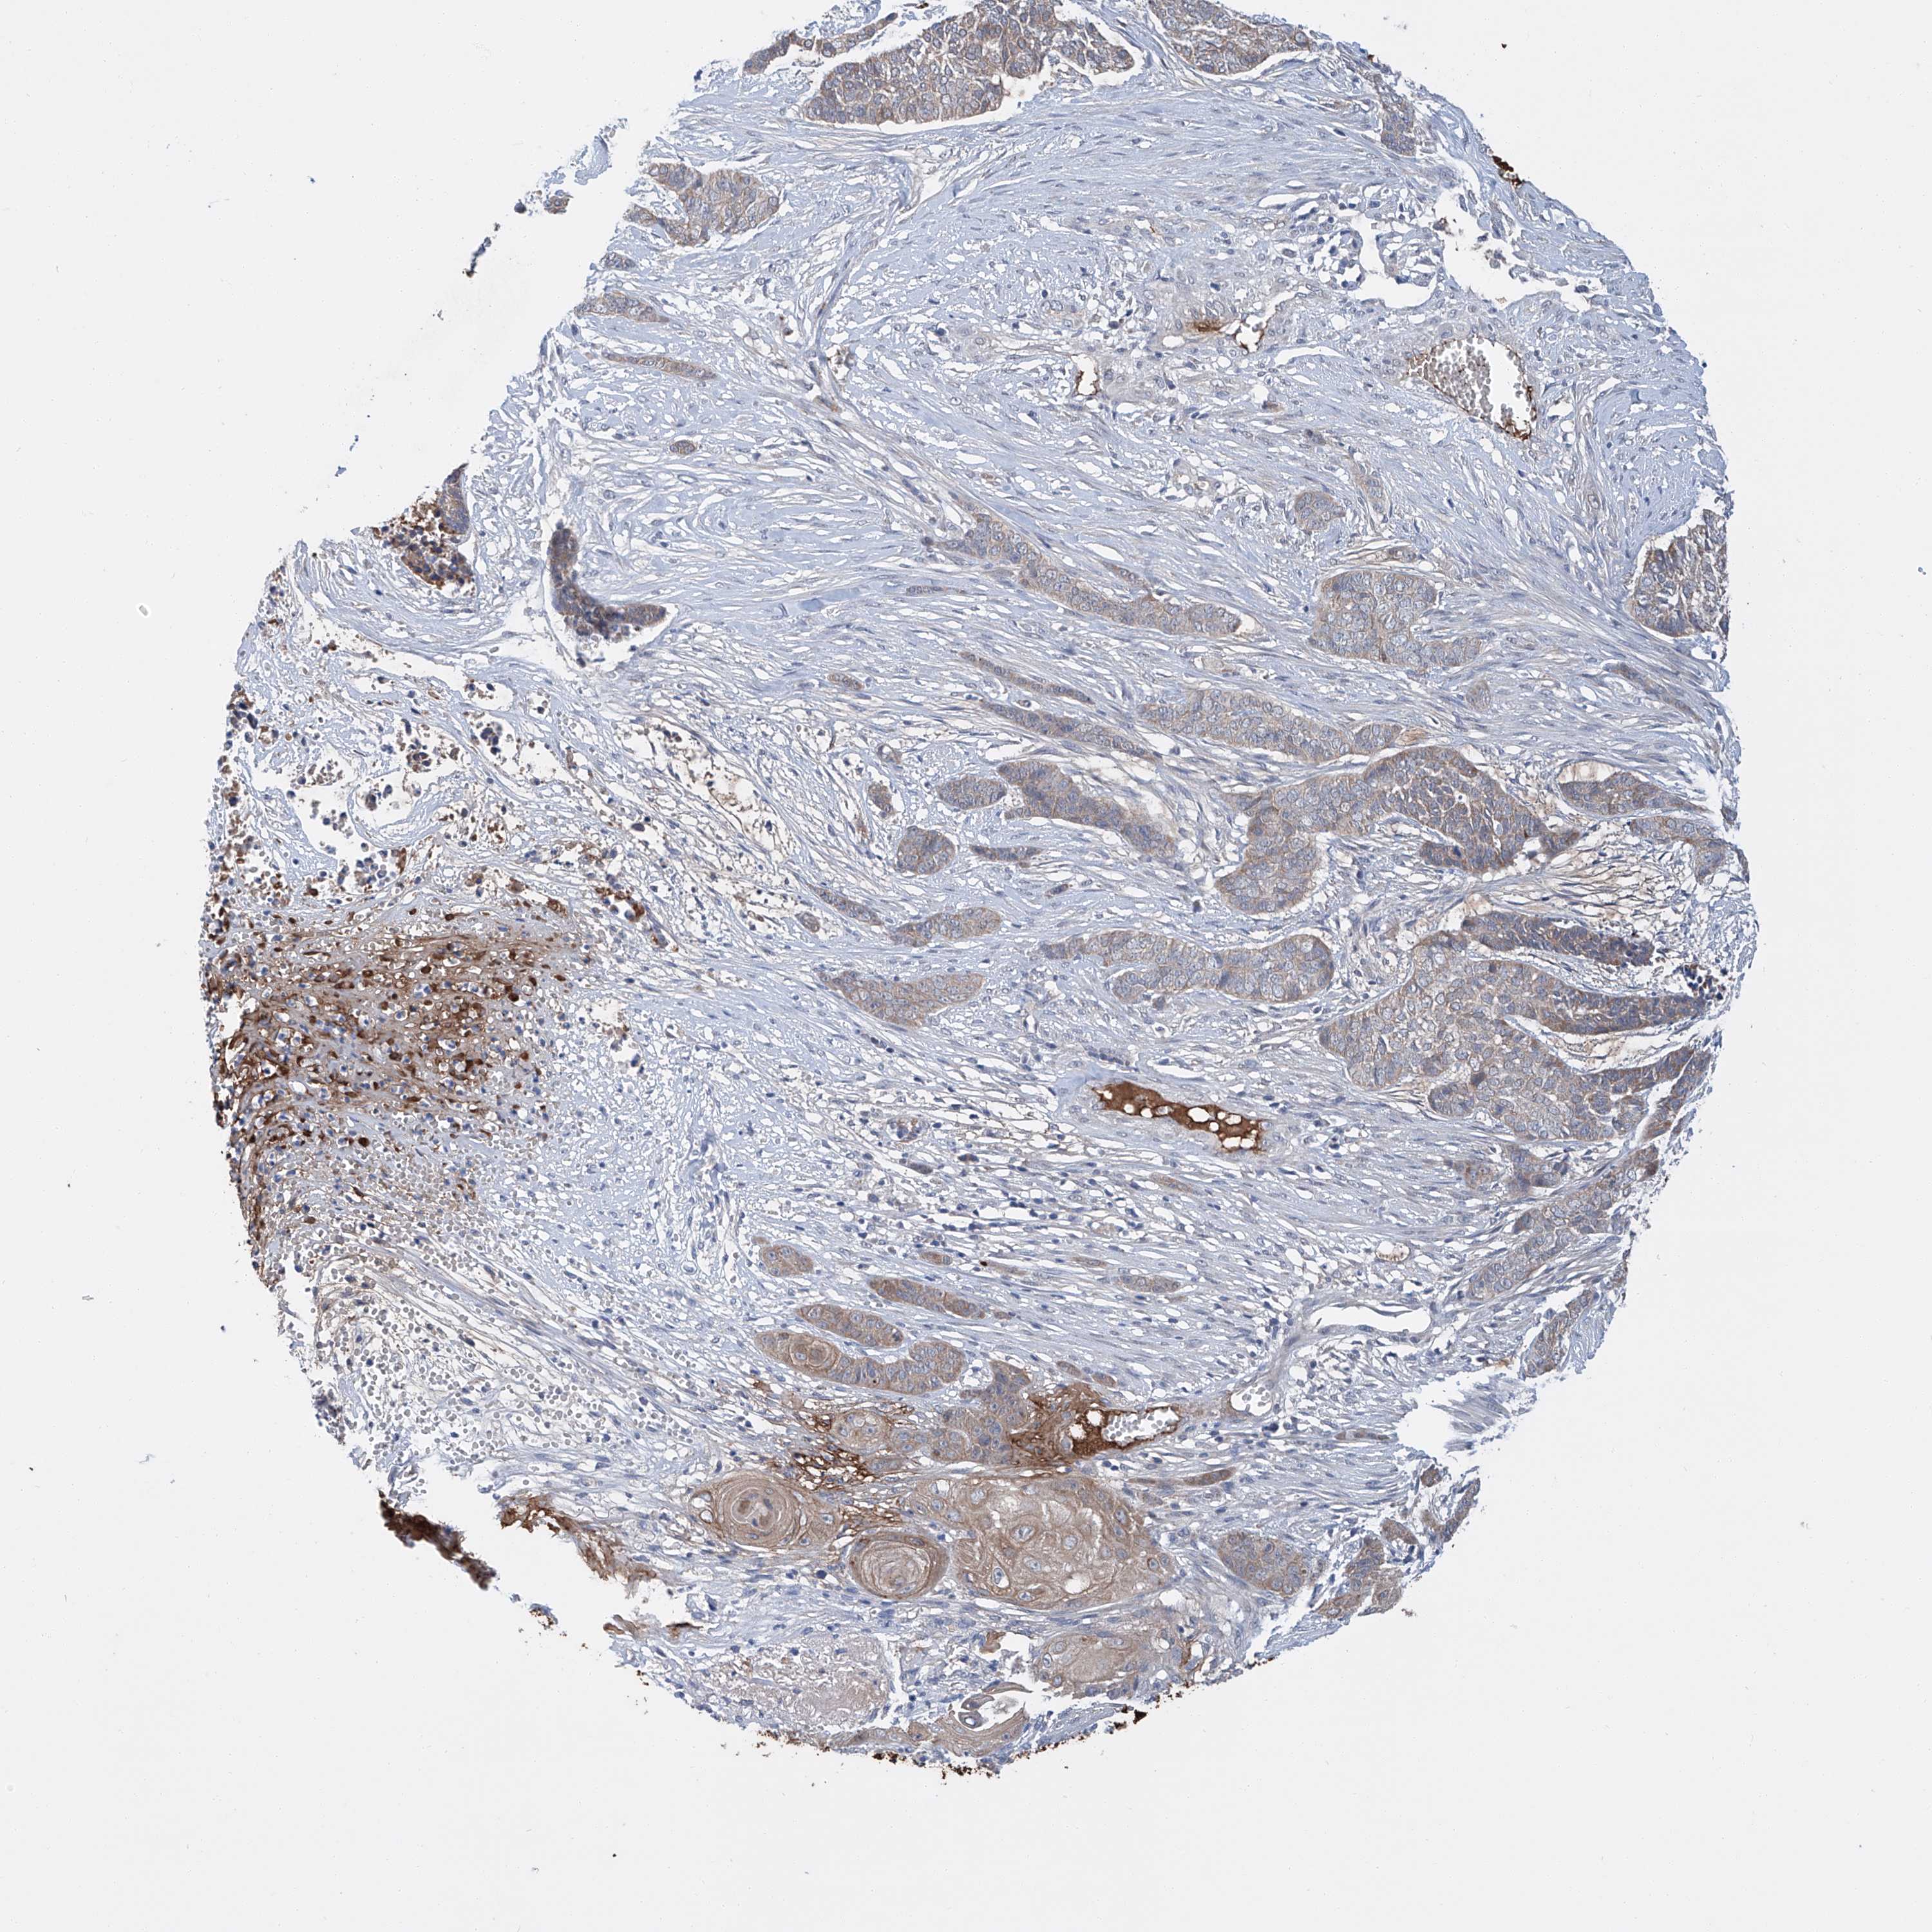

Basal cell and squamous cell cancer

SKIN CANCER - Protein expressioni

A mouse-over function shows sample information and annotation data. Click on an image to view it in a full screen mode. Samples can be filtered based on level of antibody staining by selecting one or several of the following categories: high, medium, low and not detected. The assay and annotation is described here.

Antibody stainingi

Antibody staining in the annotated cell types in the current human tissue is reported as not detected, low, medium, or high, based on conventional immunohistochemistry profiling in selected tissues. This score is based on the combination of the staining intensity and fraction of stained cells.

Each image is clickable and will lead to virtual microscopy that enables deeper exploration of all samples and also displays staining intensity scores, fraction scores and subcellular localization as well as patient and tissue information for each sample.

Antibody HPA031794

Staining

Medium

Intensity

Moderate

Quantity

75%-25%

Location

Cytoplasmic/membranous

Squamous cell carcinoma, NOS